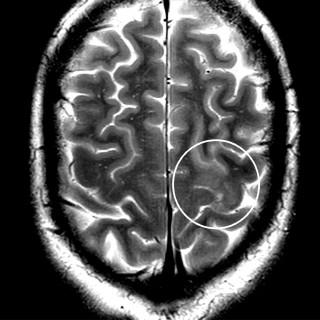

En mann i 50-årene ble brakt bevisstløs til akuttmottaket, hvor det ble påvist forhøyet osmolalt gap og aniongap. Pasientens promille på 2,1 kunne forklare det forhøyede osmolale gapet, men neppe bevisstløsheten eller det økte aniongapet. Årsaken til bevissthetstapet ble påvist først fire timer etter innleggelse, og det kliniske bildet var atypisk. En mann i 50-årene ble funnet bevisstløs utendørs. Ambulansen ankom fire minutter etter varsling, og pasienten hadde da GCS-skår (Glasgow Coma Scale) på 3, snorkende respirasjon, normal respirasjonsfrekvens (18 pust/min) og ikke målbar SpO 2. Han...